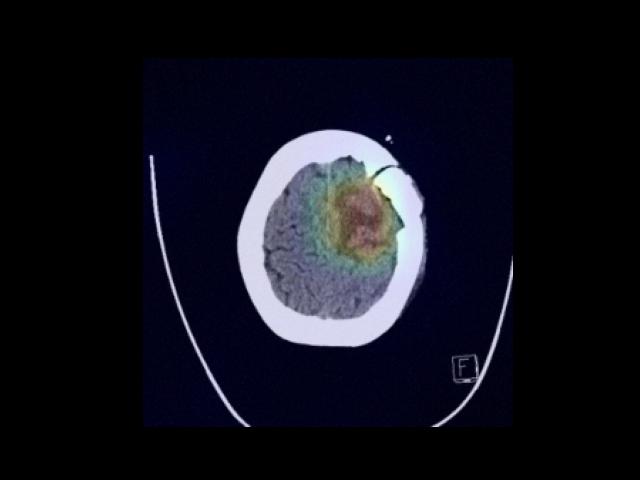

Sample Gallery